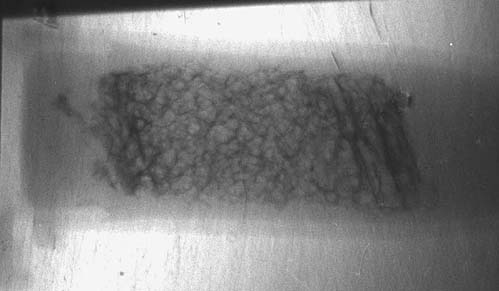

Для количественных оценок параметров маммографических диагностических аппаратов используются специально разработанные фантомы, которые представляют собой восковую пластину с различными включениями, имитирующими опухоли. На Курчатовском источнике СИ К.М.Подурец с сотрудниками выполнил эксперимент  [5], используя сертифицированный фантом RM156, и показал, что использование рефракционного метода значительно повышает чувствительность метода и позволяет обнаруживать такие объекты, как микрокальцинаты, кальцинированные сосуды и опухоли в несколько раз меньшего размера, чем при стандартной, абсорбционной съемке (см. рис.3). Новый тип контраста в сочетании с высоким качеством пучка синхротронного излучения дает возможность не только повысить информативность изображений, но и значительно снизить дозовую нагрузку на пациента. Было также установлено, что если слегка пожертвовать информативностью изображений за счет уменьшения времени экспозиции, удается при стандартном уровне обнаружения признаков заболевания дополнительно снизить дозу облучения при обследовании.

Рис. 3. Изображения фрагментов фантома, моделирующих микрокальцинаты (а), кальцинированный сосуд (б) и опухоль (в).